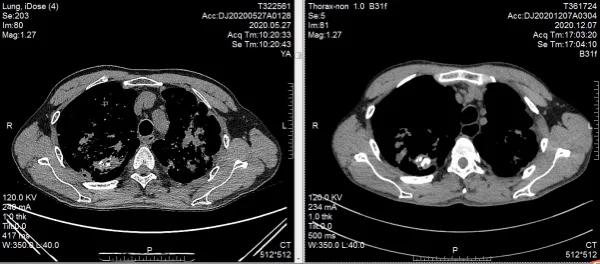

治疗12周复查胸部CT,双上肺部结核病灶较前较少,左下肺部肿瘤较前无大变化,肿瘤评估:稳定,但未再进展。抗痨治疗/抗肿瘤治疗期间,患者耐受性较好,无明显毒副反应,精神状态较前好转,咳嗽、咳痰症状明显减轻,痰涂转阴,极大增加了进一步治疗的信心。继续按原治疗方案行抗痨、抗肿瘤治疗,患者一般状况进一步好转,咳嗽/咳痰症状消失,24周复查胸部CT,双上肺结核病灶部分钙化,病情趋于稳定并向好的方向转归。左下肺肿瘤较前稍增大,肿瘤评估:稳定。

双上肺结核,抗痨治疗24周后病灶较前明显吸收(肺窗)

双上肺结核,抗痨治疗24周后病灶钙化范围增大(纵膈窗)窗)